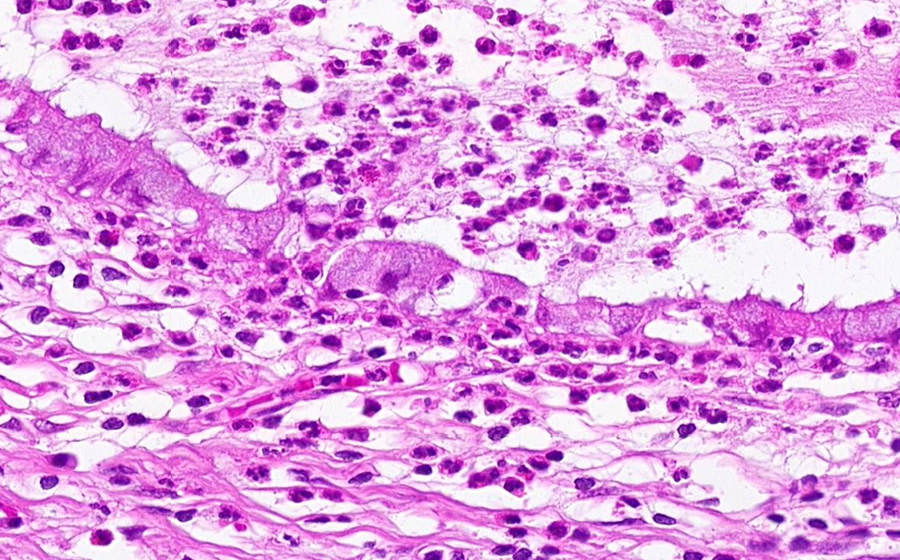

Image 5 - 400X

Slide 3 - Image 5